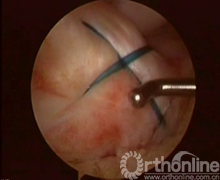

试复位成功后,于胫骨结节内1cm处做2~3cm小切口。Stryker前交叉韧带(ACL)胫骨瞄准器65°角定位骨隧道内口。其位于胫骨髁间隆突骨折创面后缘正中,外口定位于胫骨结节内下方,用1.8~2.0mm钻头钻取骨隧道后,拔出钻头,过该隧道插入18号硬膜外穿刺针,用刮勺向下压ACL体部使穿刺针穿ACL体部露头(图2)。沿针管插入PDS-Ⅱ0号可吸收线做牵引线关节内穿出,从前内侧入路牵出关节(图3)。若该针不能顺利地从ACL体部穿出,可用穿刺针自前内侧入路穿入ACL体部,自针管穿线过ACL体部,线的关节内部分与胫骨髁间隆突骨折床后部穿出骨隧道的线的未端打结连接,形成接力完成穿线过程。然后用两把止血钳分别固定该牵引线的两端。同法用前交叉韧带(ACL)胫骨瞄准器50°于胫骨创面前缘正中钻孔,PDS-Ⅱ0号牵引线于关节内穿出,自前内侧入路牵出,同样用止血钳固定两端备用。取一根长PDS-Ⅱ0号线两端自身打结做形闭环、再将环拉紧成袢形双线。分别将自前内侧入路出关节的牵引线与双线的袢形两端打结,牵拉牵引线的胫骨隧道侧,将双线拉入关节形成前后方向的袢形固定骨块(图4)。同法可于胫骨创面的两侧缘中间再钻一组骨隧道,同法引入双股PDS-Ⅱ0号横形固定骨块,固定线的未端自胫骨隧道外口引出。于胫骨结节内侧切口下方与胫骨干近端成锐角拧入一枚带垫片的空心螺钉(图5),螺钉先不拧到底。拉紧两组固定线,做后抽屉试验动作,关节内两组双线成“十字”交叉,探针探查复位状况。解剖复位后,将线拴桩捆绑于的螺钉上,此时将螺丝钉拧紧,螺钉旋进时产生很大的拉力将再次拉紧固定线,使骨块牢固固定。关节内两根双线成“十字”交叉,线绷的很紧固定非常有力。螺钉拧紧后即完成解剖复位和固定。

图1 图2

图3 图4